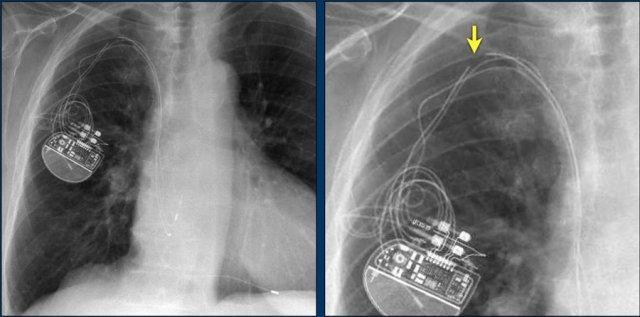

Đây là bệnh nhân có ICD với một điện cực và hai cuộn sốc điện.

Có thể thấy điện cực lưu lại của máy tạo nhịp cũ đã được tháo bỏ.

Nhiều bệnh nhân có điện cực máy tạo nhịp nội tâm mạc được để lại sau khi tháo bộ phát xung.

Tính an toàn của MRI ở bệnh nhân có điện cực máy tạo nhịp nội tâm mạc lưu lại cho đến nay vẫn chưa được nghiên cứu một cách hệ thống.

Tuy nhiên, do nguy cơ tiềm ẩn khi các điện cực này có thể hoạt động như “ăng-ten” gây nóng đáng kể – không khuyến cáo chụp MRI cho những bệnh nhân này (tài liệu tham khảo).